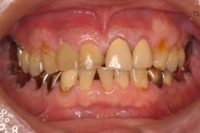

70代男性|前歯の場合

インプラント治療前

◆治療内容

前歯にインプラントを1本埋入し、アバットメントを装着。

最終的な補綴物を装着しました。